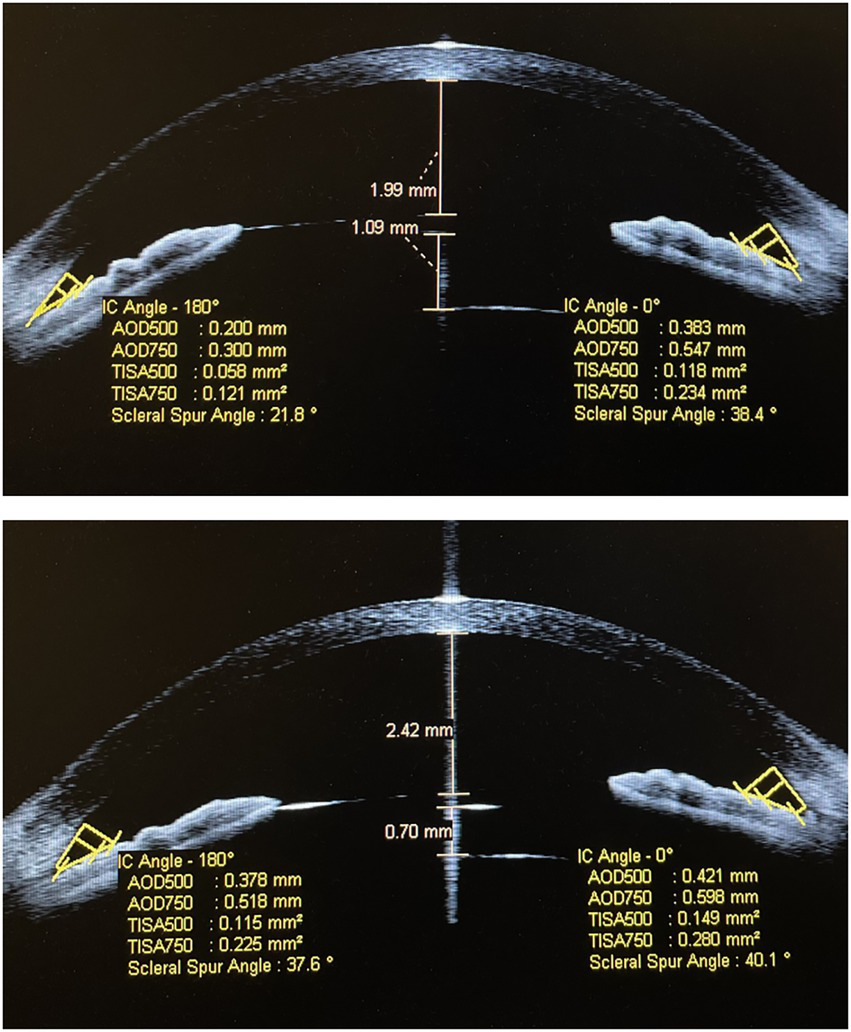

Figure 5

The implantable collamer lens position has remained well in situ for 2.5 years following rotation to the oblique position in patient C.

Figure 6

The implantable collamer lens position has remained well in situ for 3 years following rotation to the oblique position in patient D.

The safety and stability of rotation

In total, 16 of 22 patients (72.72%) had completed the 1-year follow-up. There was no intraoperative or postoperative complication. The mean vault value had changed from 747.50 ± 116.07 μm 1-week post-rotation to 586.87 ± 132.65 μm (p < 0.001). However, the SSA, AOD500, AOD750, TISA500, and TISA750 at 180° and 0° had remained well as 45.43 ± 6.26° and 46.43 ± 4.81°, 46.29 ± 6.32° and 46.75 ± 6.06°, 525.56 ± 114.22 and 522.81 ± 100.93 μm, 538.00 ± 117.31 and 535.81 ± 115.91 μm, 630.43 ± 125.55 and 666.31 ± 140.75 μm, 640.25 ± 129.38 and 673.12 ± 125.91 μm, 0.205 ± 0.053 and 0.194 ± 0.041 mm2, 0.216 ± 0.050 and 0.210 ± 0.043 mm2, 0.348 ± 0.082 and 0.342 ± 0.066 mm2, 0.360 ± 0.076 and 0.361 ± 0.072 mm2 (all p > 0.05; Supplementary Table 3; Figure 4). ICL position was stable and stayed in situ (Figures 5, 6).